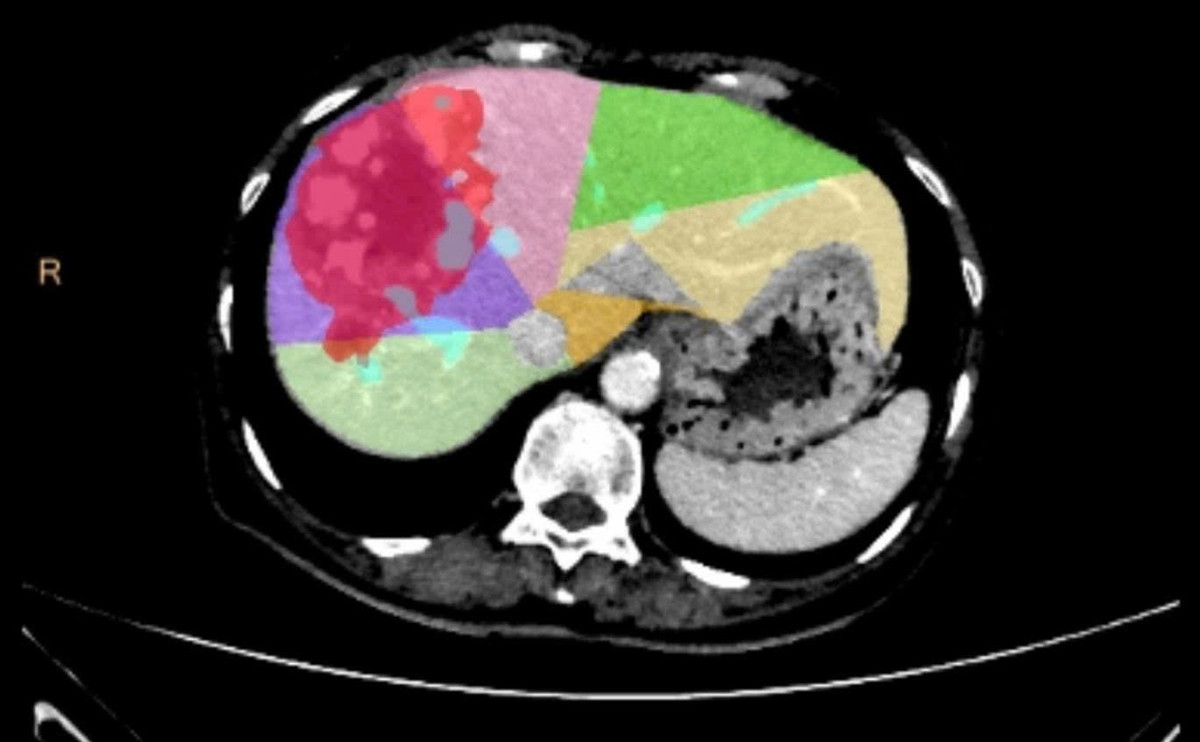

Quá trình can thiệp gây tắc tĩnh mạch cửa bên phải (PVE) - Ảnh BVCC

Trước tình huống này, các ê kíp chuyên môn đã hội chẩn liên khoa và quyết định thực hiện kỹ thuật can thiệp nút mạch gây tắc tĩnh mạch cửa bên phải (PVE). Thủ thuật này giúp chặn dòng máu nuôi phần gan phải có khối u và đồng thời thúc đẩy phần gan lành bên trái phát triển về thể tích. Chỉ sau 4 tuần, thể tích gan trái tăng lên 36,8% tổng thể tích gan, đủ điều kiện tiến hành phẫu thuật.

Gan phải và khối u giảm kích, phần gan trái lành phát triển phì đại - Ảnh BVCC